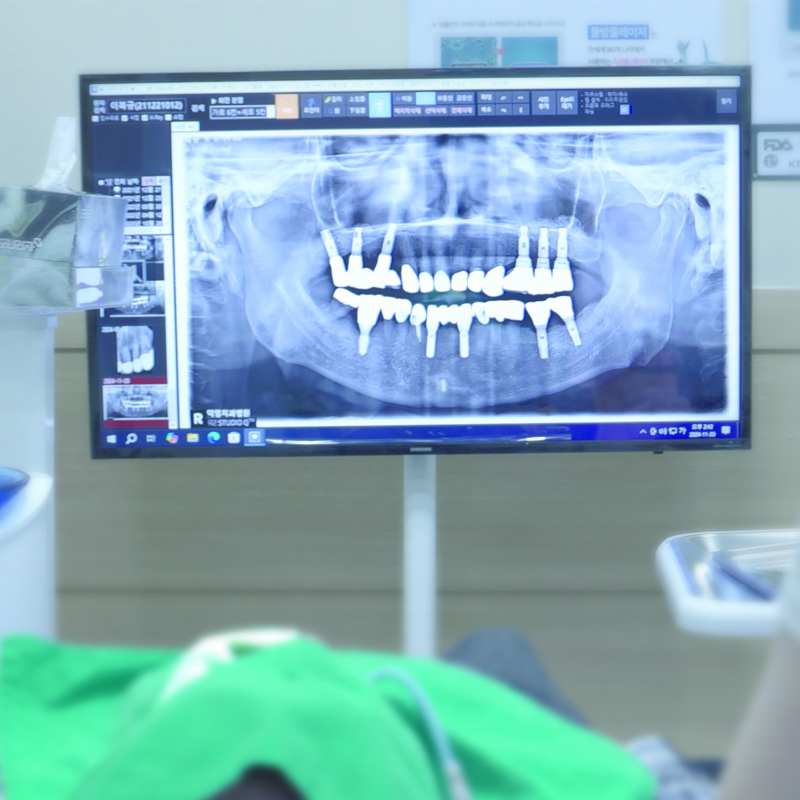

임플란트, 전문적인 관리가 중요합니다.

초기에는 가벼운 잇몸 염증으로 시작되지만, 진행되면 뼈 손실까지 초래하여 임플란트를 유지하기 어렵게 만들 수 있습니다.

로이스치과는 최첨단 장비와 임플란트 전문 의료진을 통해

환자 여러분의 소중한 임플란트를 안전하고 건강하게 관리해드립니다.